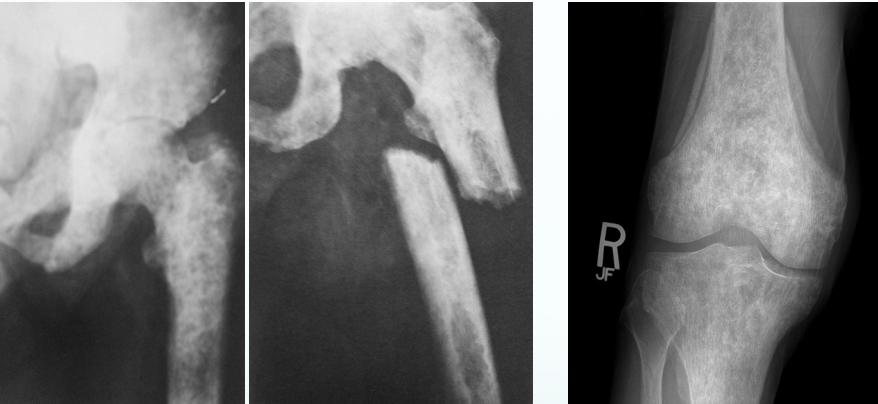

Metastatic - Prostate

- Osteoblastic in ca prostate

Source: Orthopedic Radiology. A Greenspan. Lippincott-Raven